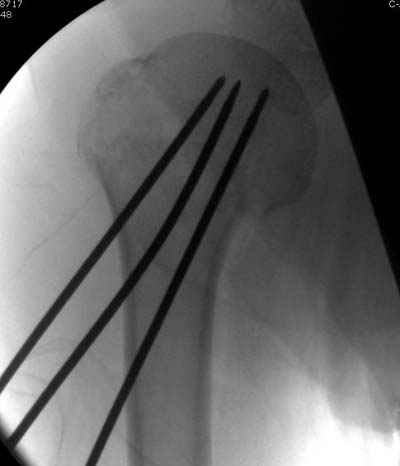

Здравствуй Женя. Во первых спицы, вводимые в головку плеча ретроградно, никогда не имели V-образную форму, если говорить о методике моей операции ЦИТО. Чтобы легче было запомнить Y-образную форму, вспомни крепление новогодних елочных шаров - очень демонстративно. Кроме того если ты внимательно посмотришь, то увидишь, что вся конструкция имеет некоторую кривизну по плокскости, величину, которой ты можешь задать сам. Сначала мы проводим проксимальный пучок, а в момент пересечения линии перелома мы

ротируем спицу таким образом, чтобы дистальный изгиб прямо противодействовал смещающим силам - поврот за ушко под контролем ЭОПа. Дистальный пучок стараемся провести так, чтобы его бранши расклинились и прошли по обе стороны предыдущего пучка, что создает дополнительное напряжение на

протяжении контакта. Для оценки правильности проведения спиц очень важно, чтобы ЭОП стоял строго перпендикулярно плоскости сустава, в противном случае - в рентгене есть эффект отбрасывания тени - прохождение косого луча дает удлиненное изображение спиыц и создается впечатление, что спица стоит уже в субхондральном слое. На первых операциях у нас было довольно частое несовпадение длины контрольной спицы и мы провизорно добавляли от 0,5 до 1,0 см уже на фиксирующем пучке. Входные отверстия лучше располагать по наружной и передней поверхности плеча на расстоянии не менее 2-х диаметров головки.

Такой выбор входных отверстий обусловлен прямой возможностью попадания в малый и большой бугорки за счет изгиба спиц по длине и отражения из от внутреннего кортикала проксимальнее точки введения. Поскольку анатомически бугорки не составляют артикулирующую поверхность, то некоторое выстояние спиц только усилит стабильность. Входное отверстие мы используем 6 мм в диаметре, для эффективного раскрытия петли-пружины. Спицы перед проведением

проверяем на достаточную эластичность и упругоустойчивость, мягкие спицы отбраковываем. В данном примере создалось впечатление, что одна бранша V-спицы скользнула по картикалу снаружи? Все это безболезненно можно переделать, расширив теже отверстия, изогнув спицы, повернув их в разные стороны и добавив еще пучки Y-ОБРАЗНЫХ, а не V-образных (эти пучки выталкивает, особенно если они прямые - пружина работает в обе стороны).